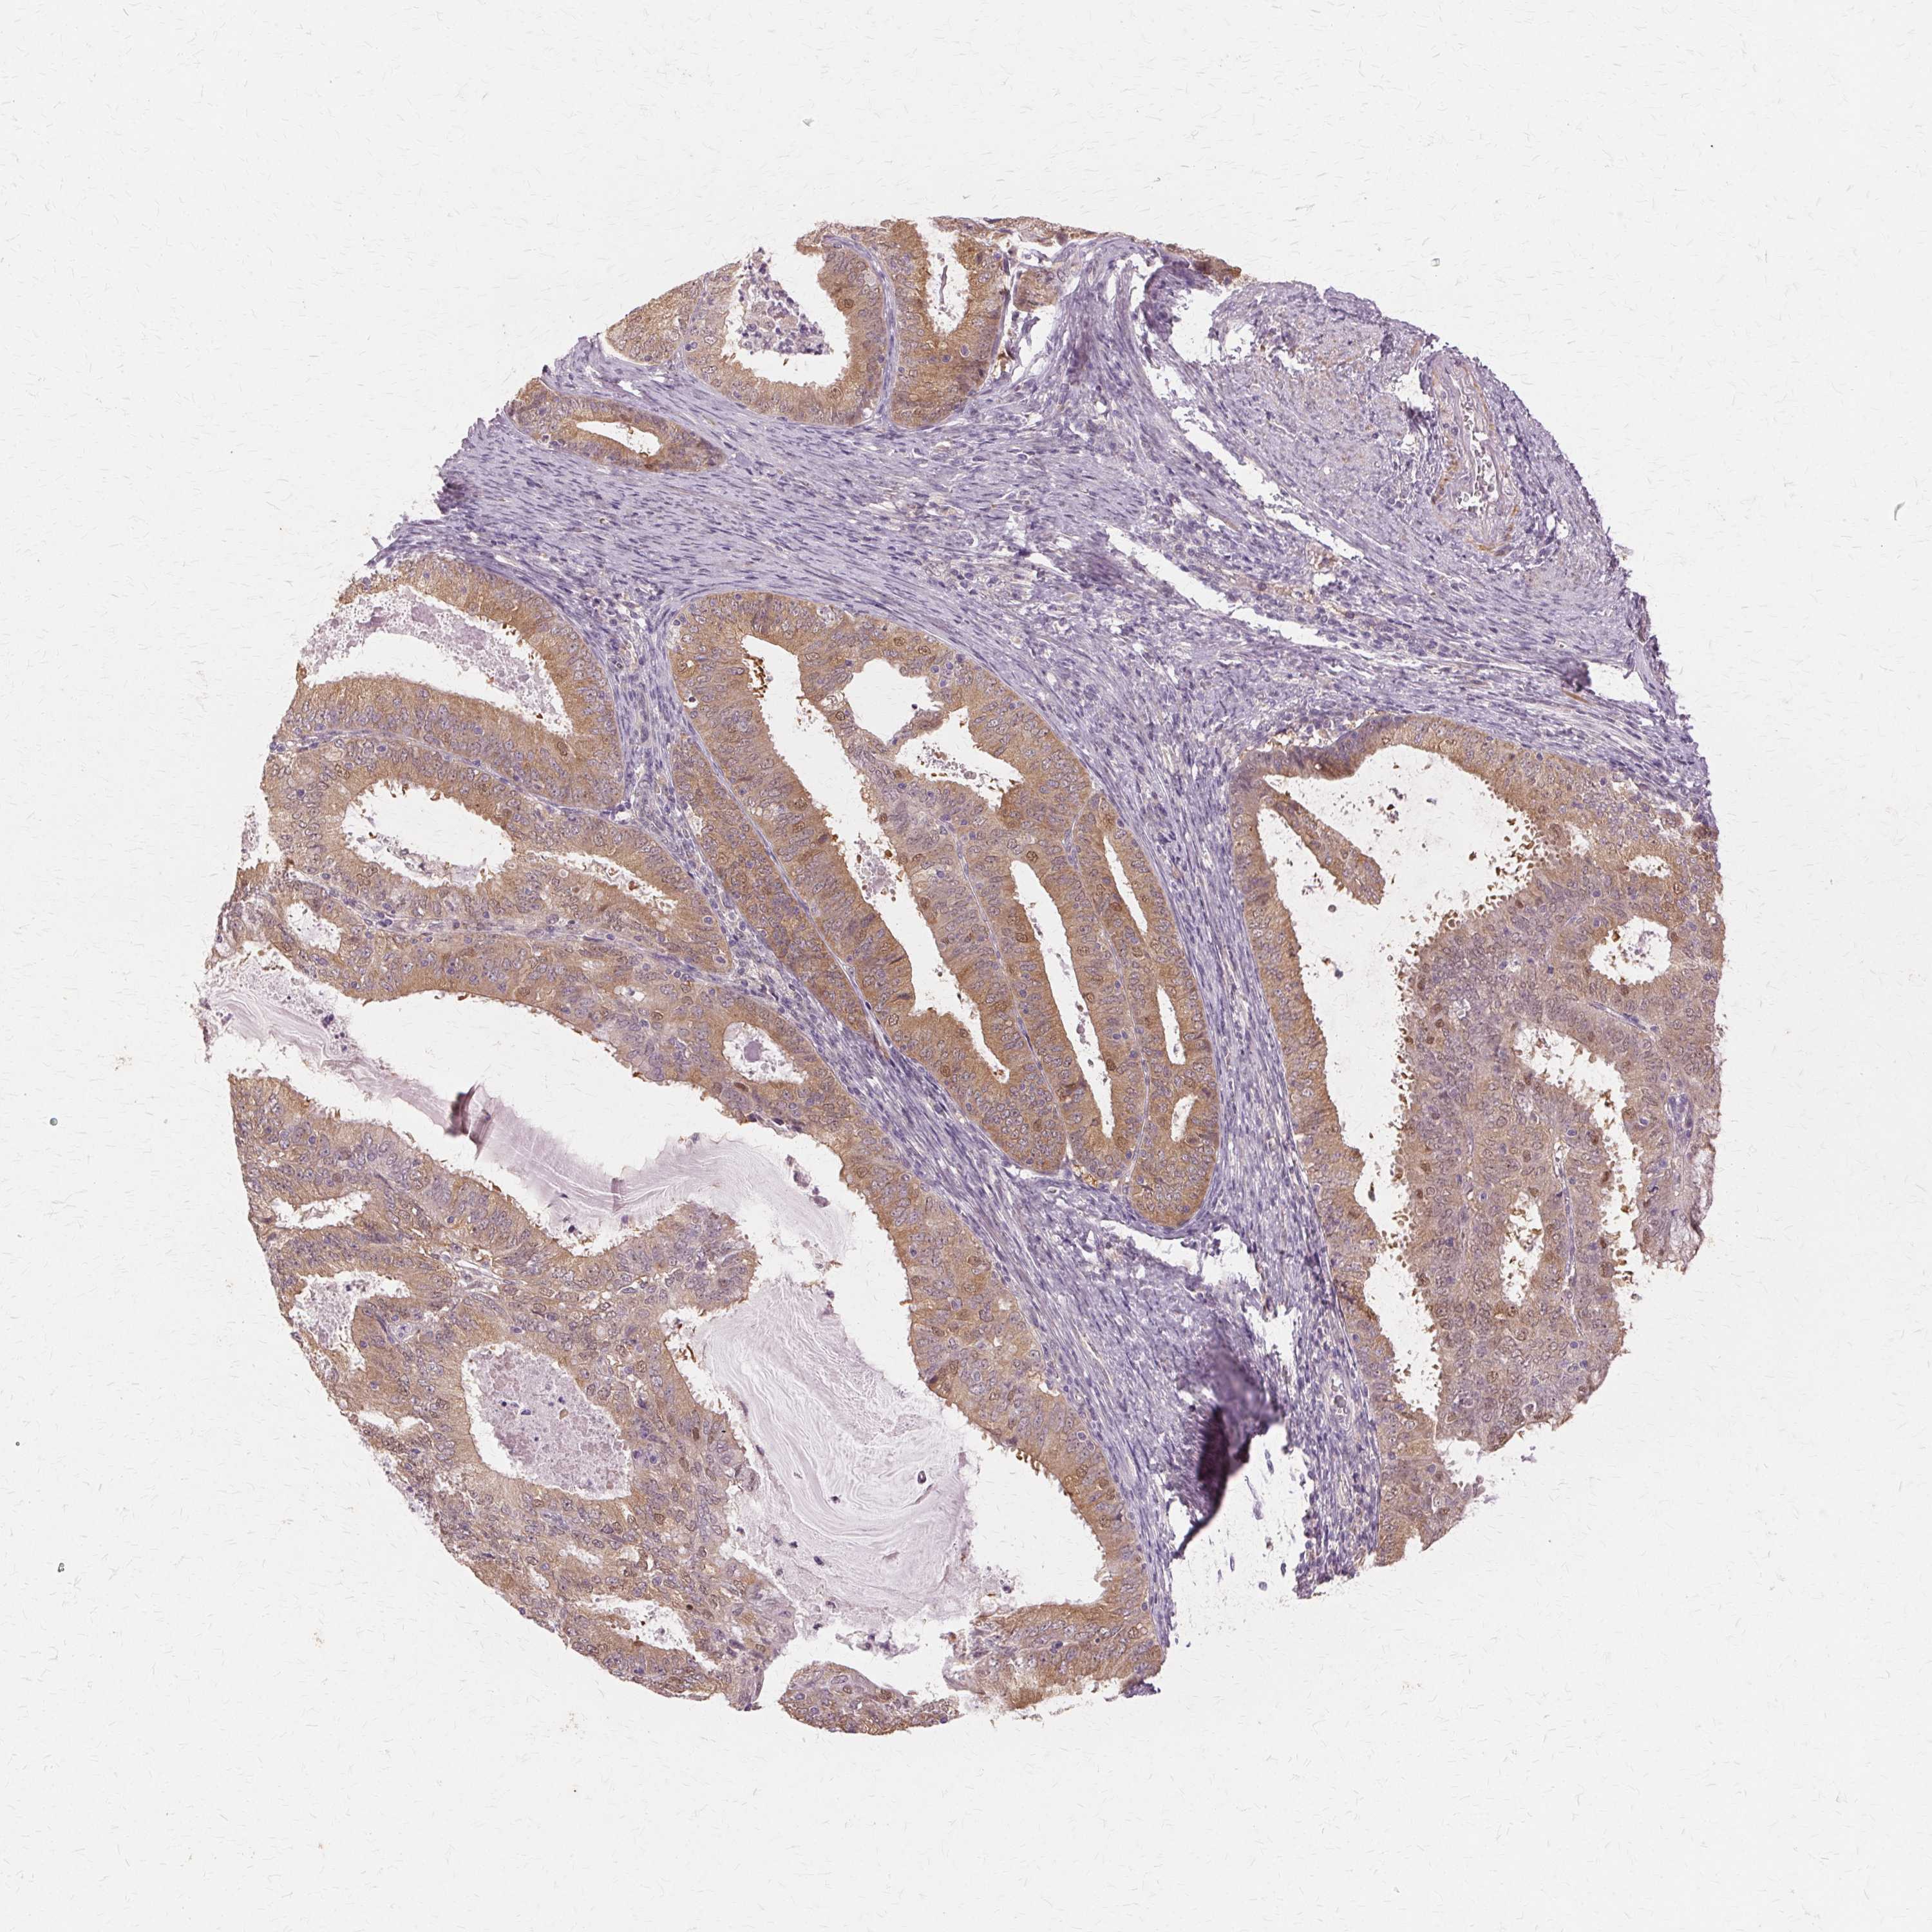

ENDOMETRIAL CANCER - Protein expressioni

A mouse-over function shows sample information and annotation data. Click on an image to view it in a full screen mode. Samples can be filtered based on level of antibody staining by selecting one or several of the following categories: high, medium, low and not detected. The assay and annotation is described here.

Note that samples used for immunohistochemistry by the Human Protein Atlas do not correspond to samples in the TCGA dataset.

Antibody stainingi

Antibody staining in the annotated cell types in the current human tissue is reported as not detected, low, medium, or high, based on conventional immunohistochemistry profiling in selected tissues. This score is based on the combination of the staining intensity and fraction of stained cells.

Each image is clickable and will lead to virtual microscopy that enables deeper exploration of all samples and also displays staining intensity scores, fraction scores and subcellular localization as well as patient and tissue information for each sample.

Antibody HPA005525

Antibody HPA064708

Antibody CAB012459

Staining

High

Medium

Low

Not detected

Intensity

Strong

Moderate

Weak

Negative

Quantity

>75%

75%-25%

<25%

None

Location

Nuclear

Cytoplasmic/membranous

Cytoplasmic/membranous,nuclear

Adenocarcinoma, NOS

Neoplasm, malignant, NOS

Adenocarcinoma, metastatic, NOS